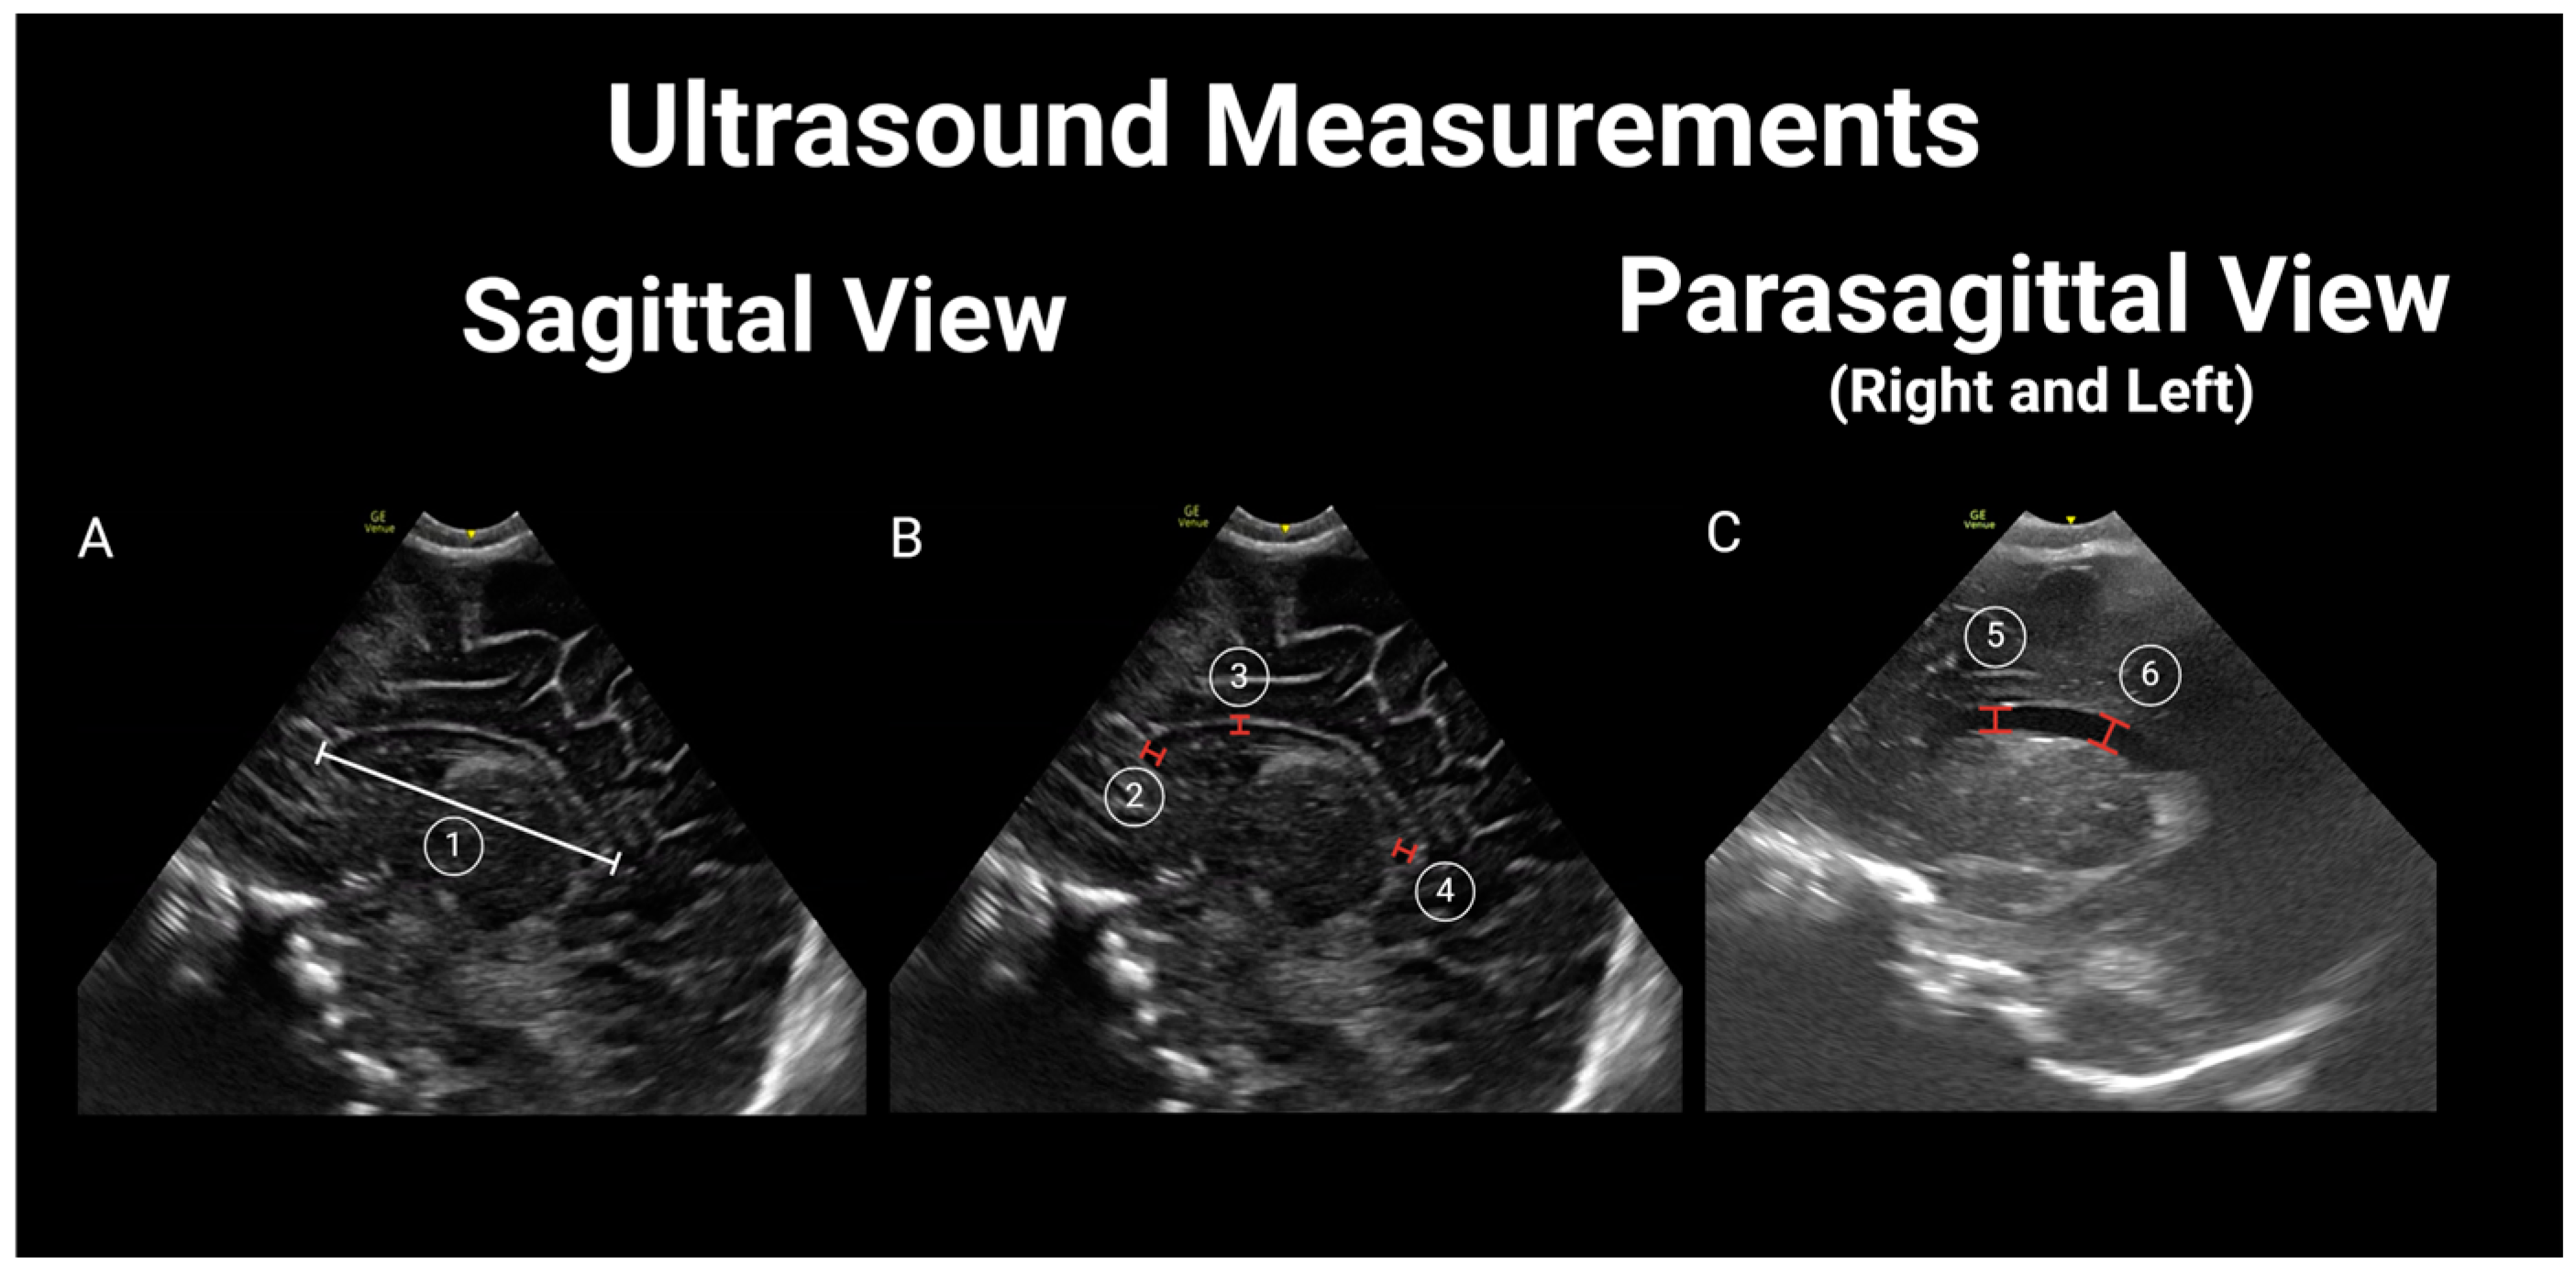

2.3. Brain US Protocol

2.4. Image Interpretation and Analysis